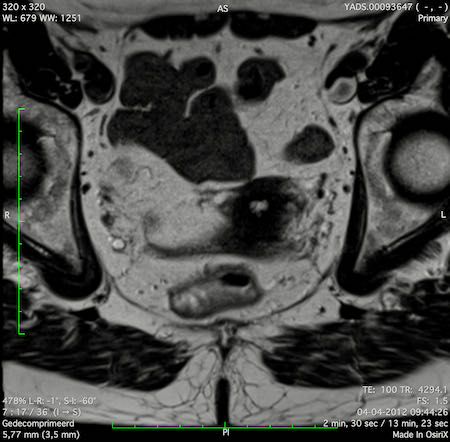

Hình ảnh

Các hình ảnh được cung cấp cho thấy ung thư biểu mô tế bào nhẫn với tình trạng dày lan tỏa thành trực tràng, hình ảnh bia bắn điển hình, và sự xâm lấn mỡ mạc treo trực tràng.